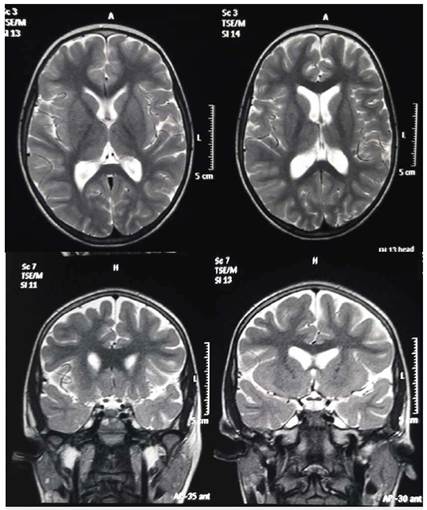

Durante el estudio de la epilepsia se solicitaron múltiples paraclínicos que incluyeron, además de resonancia magnética cerebral con espectroscopia cuyo resultado fue normal, una nueva telemetría de 96 horas que mostró 3 crisis focales (figura 2) con actividad epileptiforme frontal bilateral con predominio basal derecho y generalización secundaria. Se realizó PET-CT que evidenció moderada a severa disminución del metabolismo en región temporal izquierda. Adicionalmente se hizo estudio completo de inmunodeficiencias y enfermedades metabólicas que cuáles fueron negativos (figura 3).

Figura 4 Resonancia Magnética Nuclear de cerebro. Tomado de soportes de historia clínica provistos por la acudiente de la paciente.